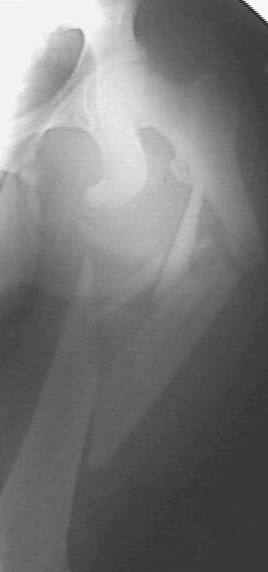

Больной 20 лет. Автодорожная авария 06.07.03.

Диагноз : оскольчатый сегментарный перелом правого бедра. Перелом лобковой кости со смещением, разрыв лобкового сращения. Планируем остеосинтез бедра пластиной. (гвоздей с блокировкой нет). Сшивание симфиза. Как поступить с переломами лобковой кости? Сергей Зырянов НСО г. Куйбышев